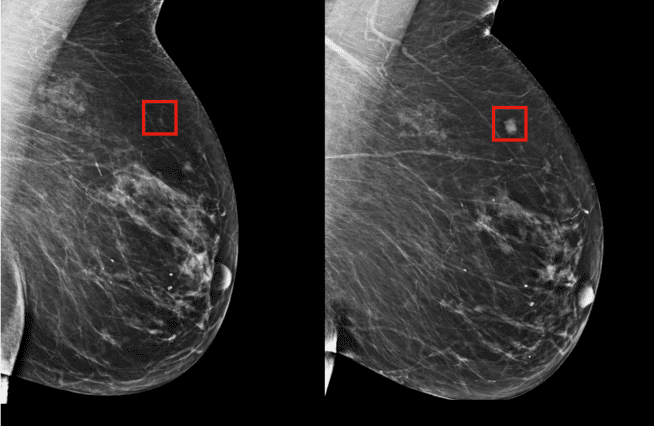

El equipo del laboratorio de Inteligencia Artificial del MIT y el Hospital de Massachusetts han creado un nuevo modelo de aprendizaje automático que puede predecir el riesgo probable de un paciente para desarrollar cáncer de mama, a partir de una mamografía.

El algoritmo ha sido entrenado con la información de más de 90 mil mamografías, lo que le permitió aprender los patrones del tejido mamario que son los principales precursores de tumores malignos.

El modelo tuvo una precisión de 31 por ciento en todos los pacientes con cáncer de alto riesgo, mientras que los tradicionales obtuvieron una precisión de apenas 18 por ciento.